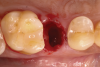

Following local anesthesia via infiltration of 2% xylocaine with 1:100,000 epinephrine, a sulcular incision was carried out on both the buccal and lingual aspects of the tooth to protect adjacent soft tissues during tooth elevation. Periotomes were used following the long axis of the tooth to provide careful elevation of the residual root of the maxillary second premolar. After tooth removal, the extraction socket was inspected and completely degranulated with curettes. A saline solution was used to irrigate the site, and bleeding from the socket walls was stimulated (Figure 2).

Fig 2. Minimally traumatic exodontia was performed to preserve the integrity of the socket walls and adjacent soft tissue.

Figure 2